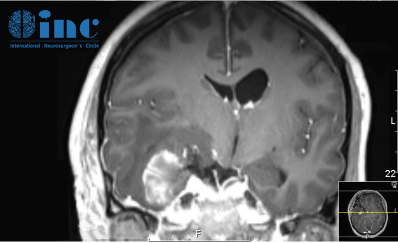

術(shù)后一周復查磁共振增強,術(shù)區(qū)高信號為暫時未吸收的止血材料等

(術(shù)后一周復查磁共振增強,術(shù)區(qū)高信號為暫時未吸收的止血材料等)